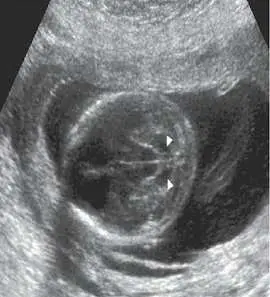

35 歲孕婦經轉診至門診, G2P0AA1 ,無家族病史,目前妊娠 22 週。該孕婦於產前超音波檢查時,結果如圖所示,該異常特徵( sign )為何?

本題考查產前超音波的特徵性影像表現(signs)與其對應診斷。35 歲孕婦妊娠 22 週,產前超音波顯示異常。四個選項分別對應四種不同產前超音波特徵,每種特徵對應特定的先天異常。正確答案需依超音波圖像的實際外觀判斷。

影像分析:

超音波圖像顯示胎兒頭部橫切面,於後腦窩(posterior fossa)處可見小腦(cerebellum)形態異常:小腦半球(cerebellar hemispheres)呈向前彎曲、弧形壓縮的外觀,並向前包繞腦幹(brainstem),形狀狀似香蕉,橫切面下小腦半球之間的分界模糊、後腦池(cisterna magna)消失。此為**banana sign(香蕉徵)**的典型表現,是 Arnold-Chiari II 型畸形(Chiari type II malformation)的間接超音波標誌,提示存在開放性神經管缺損(open neural tube defect),最常見為脊髓脊膜膨出(myelomeningocele)。圖中白色箭頭(arrowheads)標示被壓縮前移的小腦組織。

(A) double bubble sign(雙氣泡徵) 雙氣泡徵出現於腹部橫切面,顯示胃(stomach)與擴張的近端十二指腸(proximal duodenum)形成兩個相鄰圓形無回音區(fluid